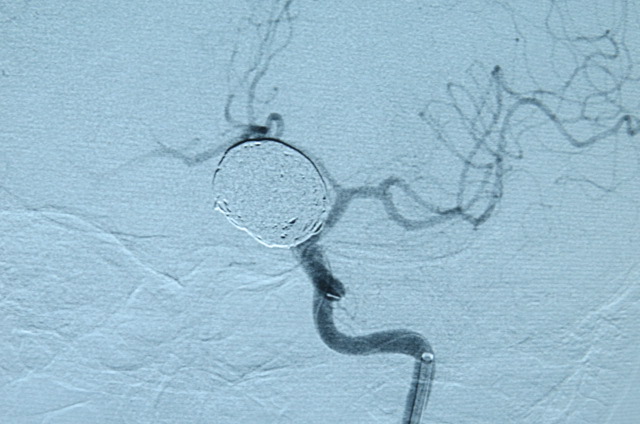

بیمار خانم 63 ساله می باشد به علت سرگیجه به بیمارستان مراجعه کرده است ، در MRI ضایعه بزرگ به اندازه 25MM گرد شبیه تومور مشاهده شده که در آنژیوگرافی مغزی ضایعه آنوریسم مغزی تشخیص داده شد،بیمار توسط تیم جراحی به سرپرستی دکتر کهنسال تحت جراحی بسته ( اینترونشن ) مغزی قرارگرفت و آنوریسم مغزی کاملا بسته شد و بیمار به بخش منتقل شد .

بر اساس گزارش به عمل آمده حال عمومی بیمار خوب می باشد . این عمل در شمال کشور و گلستان برای اولین بار انجام شد.